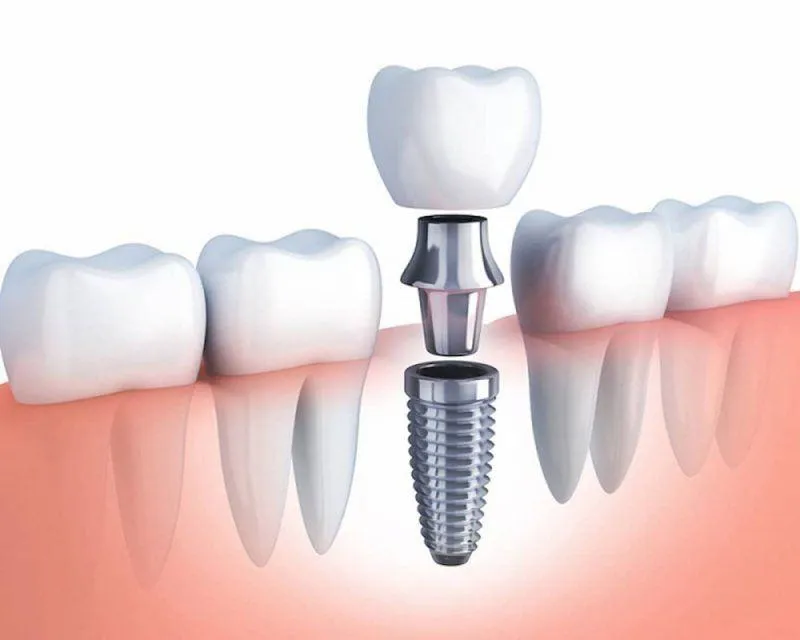

Phục hình răng sứ trên Implant được chỉ định trong các trường hợp mất răng một chiếc hoặc toàn hàm. Phương pháp này hiện rất phổ biến

Phục hình răng sứ trên Implant là phương pháp nha khoa khá phức tạp, đòi hỏi thực hiện bởi nha sĩ tay nghề cao và cơ sở